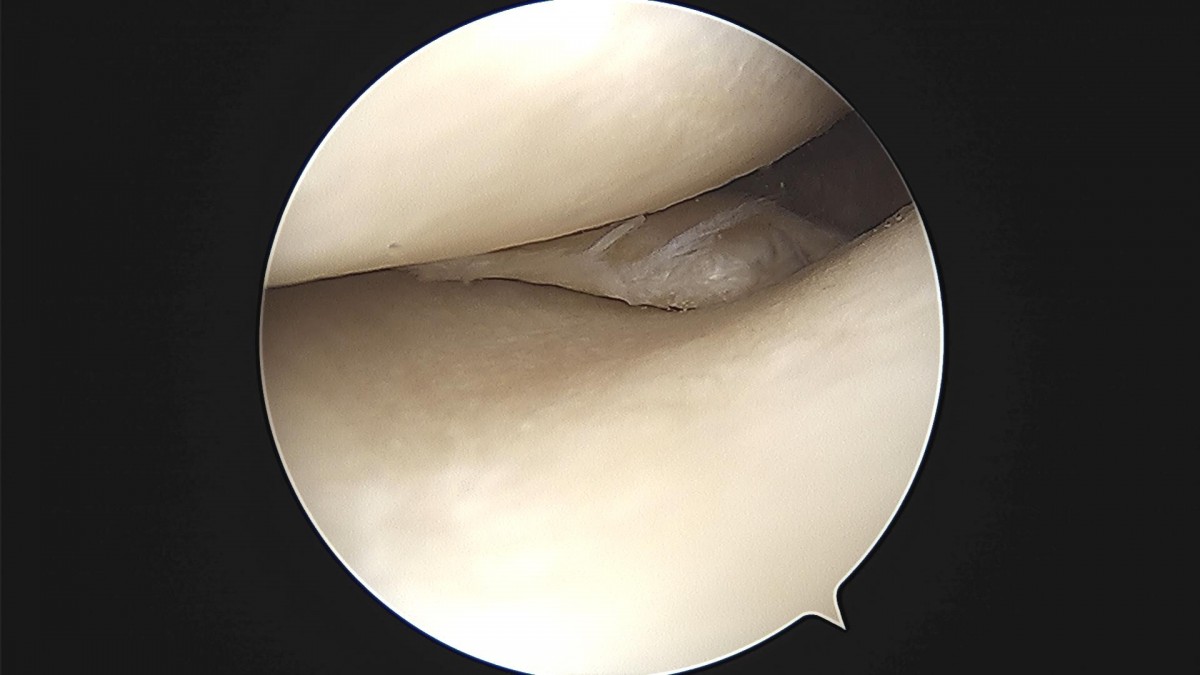

배우한 원장님 무릎 반월상 연골판 절제술 김상O 환자

7f9ebc16eacada2d783f417d78aef718_1711951770_8858.jpg